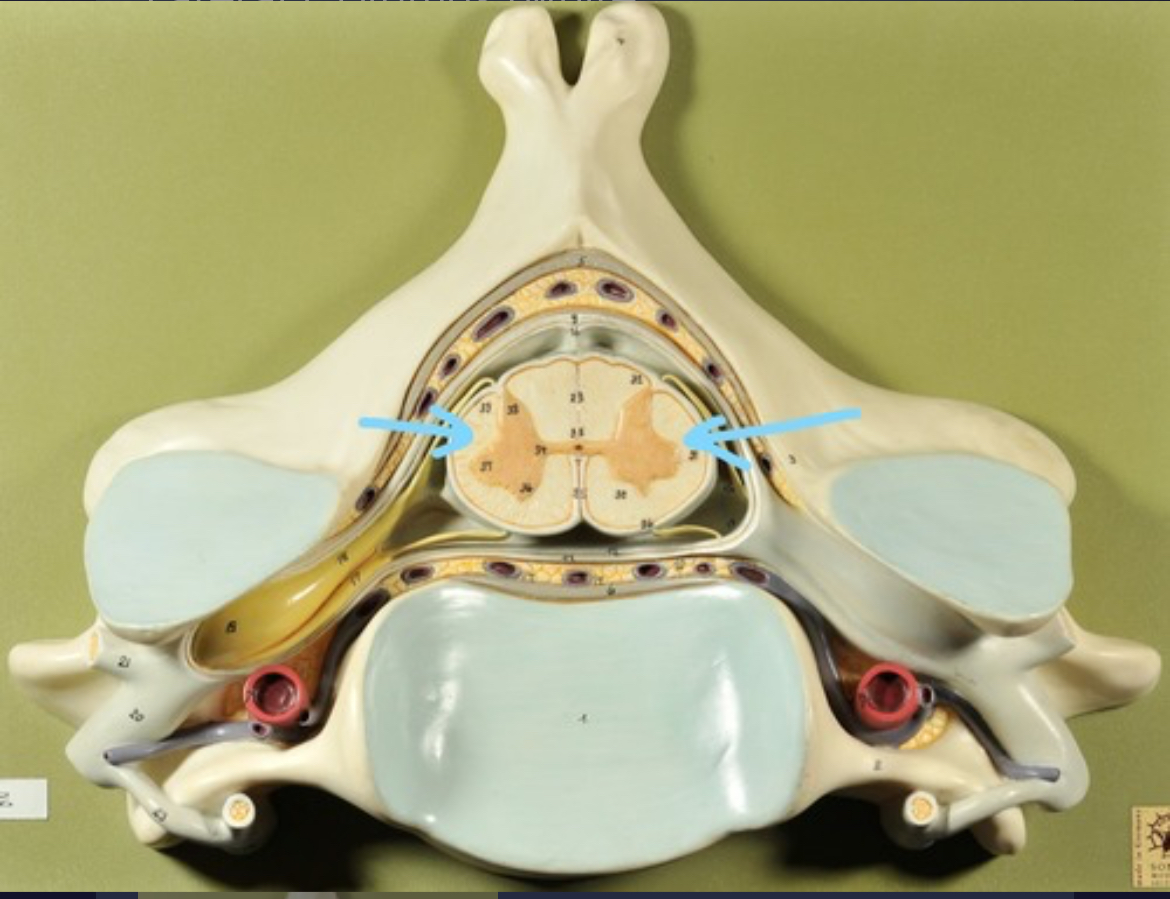

Dura mater (outermost layer)

White matter of spinal cord

Gray matter of spinal cord

Ventral horns (of gray matter)

Lateral horns

Dorsal horns

Anterior columns of white matter

Lateral columns of white matter

Posterior columns of white matter

central canal of spinal cord

Pia matter

Subarachnoid space

Arachnoid matter

Subdural space (brown line)

Dura matter

Epidural space

Dorsal root ganglion

Dorsal root

Ventral root

Spinal nerve